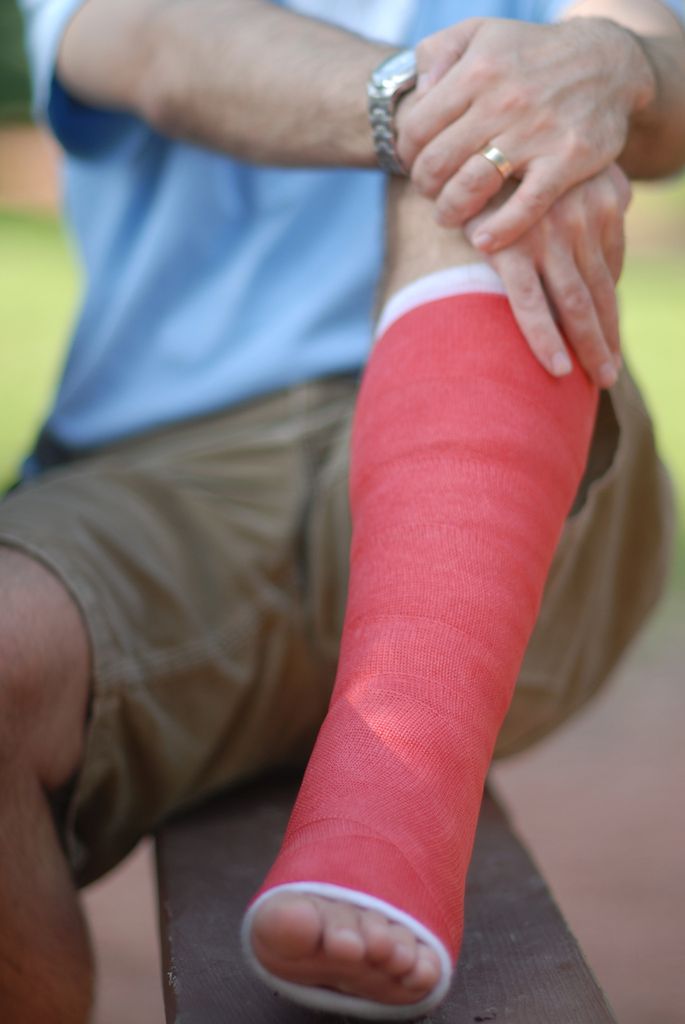

/ 14Osteoporoza - złamania

Obraz

© ItzaFineDay, lic. CC BY 2.0

Objawy osteoporozy: złamania szyjki kości udowej

Złamanie biodra następuje zwykle w wyniku upadku, u pacjentów z osteoporozą uszkodzenie to może powstać w banalnych okolicznościach, przy czym leczenie może być skomplikowane ze względu na niską gęstość i jakość tkanki kostnej.